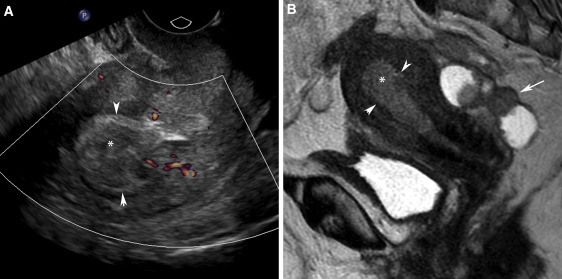

- Ultrasonografi: Organların büyüklüğünü ve yapılarını görüntüler. Hiperplazi şüphesi olan bölgelerde yumruları tespit edebilir.

- MRI veya BT Taraması: Detaylı iç görüntüler sağlayarak, anormal büyümeleri net bir şekilde gösterir.